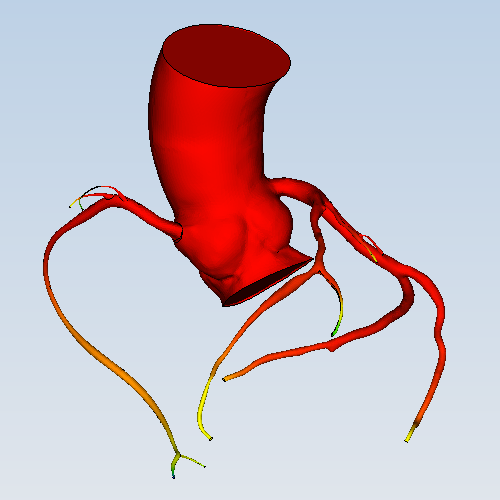

- 59 冠状动脉含主动脉根部血流动力学仿真

流体 | 冠状动脉含主动脉根部血流动力学仿真APP描述冠状动脉(含主动脉根部)内的血液流动情况。血液在冠状动脉里流动过程中,会根据血管形态改变流速与压力,从而影响冠状动脉上疾...